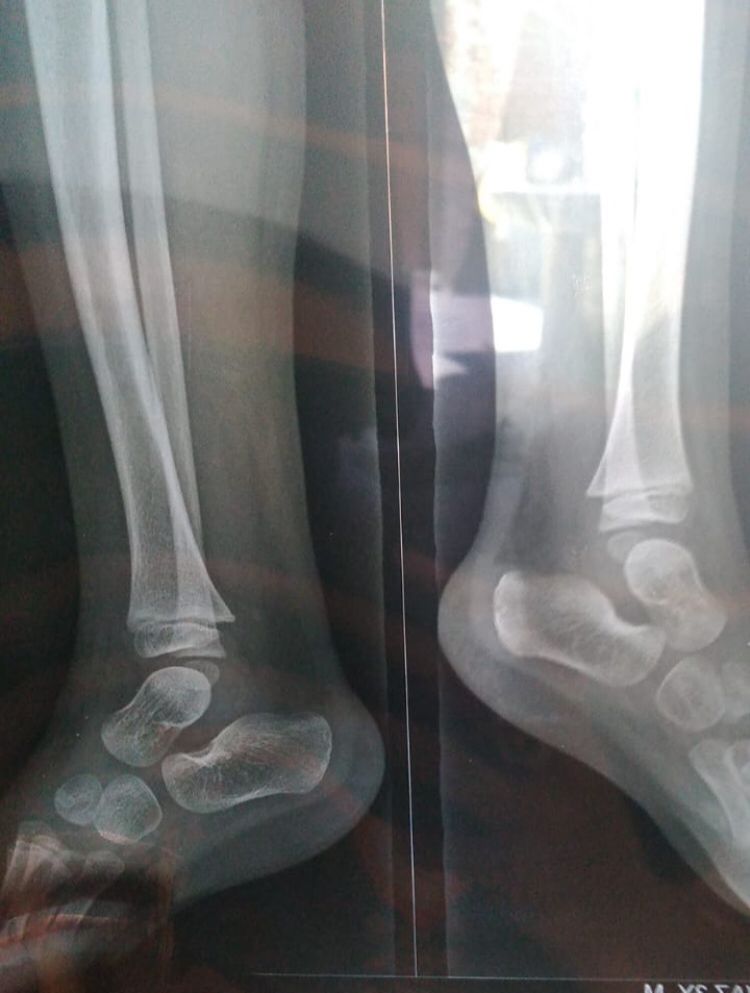

Please have look his x-ray

4 years ago

please have a look his x-ray report

x-ray